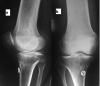

Objective: to assess twenty two cases of isolated PCL avulsion fractures from tibial insertion, arthroscopically treated with suture pull technique, and to evaluate achieved clinical outcomes in terms of radiographic laxometry (objective) and Lysholm scale (subjective).

Material and method: Study includes 22 cases operated between April 2014 and March 2017. Patients less than 18 years old, presentation after 3 weeks of injury, concomitant injury in the same limb, with open wounds or with comminuted avulsed fragment were excluded from the study. All cases were MRI proven. All arthroscopic suture fixation technique was used in all cases. Follow up was done at 3 weeks, 6 weeks, 3 months, 6 months and 12 months. Mean follow up was one year. Subjective complaints, Knee flexion, Lysholm score and stress radiographs were noted.

Results: Average Lysholm score was 96.3. Seventeen patients had excellent results and Five had good results based on Lysholm scores. In two patients, grade 2 laxity (5-10 mm) was present on stress radiographs but there were no clinical complaints. All patients achieved osseous union and had no functional limitation. Three Patients developed arthrofibrosis initially but gained functional range later.